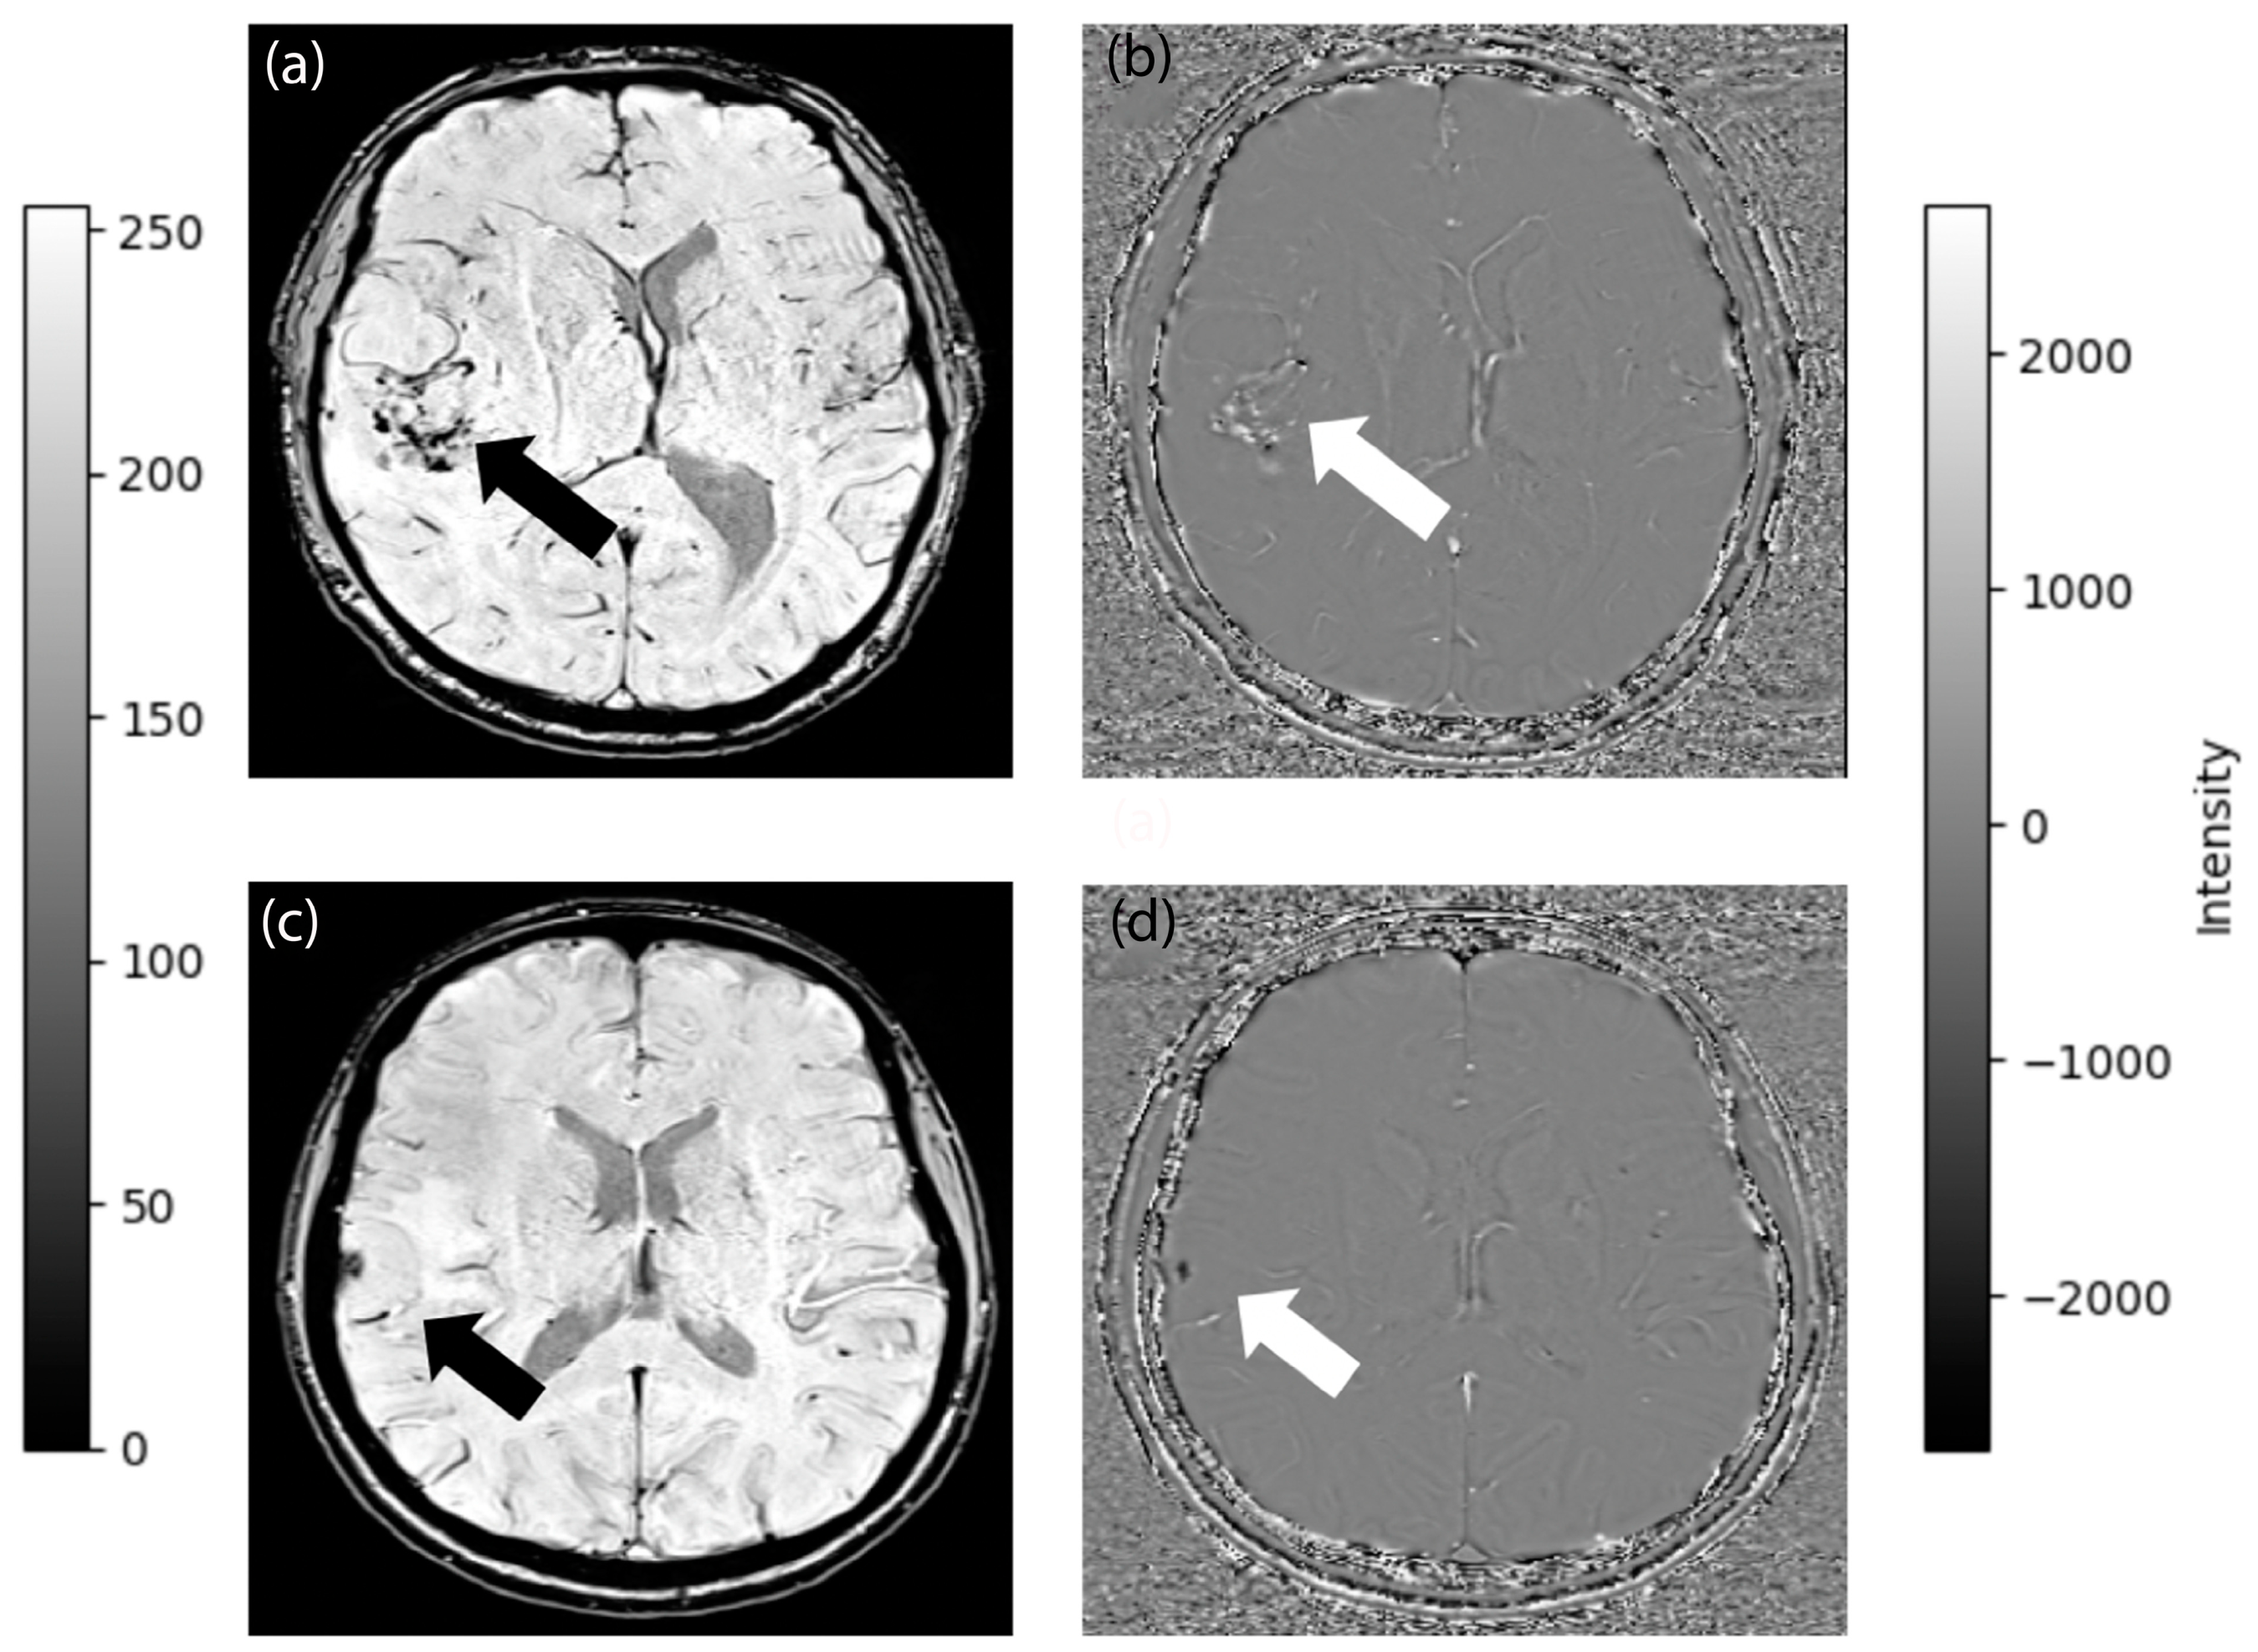

2.5. Image Processing